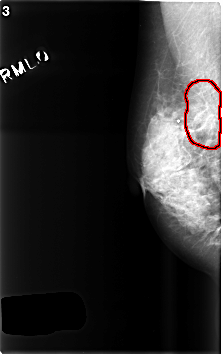

FILE: C_0418_1.RIGHT_MLO.OVERLAY

TOTAL_ABNORMALITIES 1

ABNORMALITY 1

LESION_TYPE MASS SHAPE ARCHITECTURAL_DISTORTION MARGINS SPICULATED

ASSESSMENT 5

SUBTLETY 3

PATHOLOGY MALIGNANT

TOTAL_OUTLINES 1

BOUNDARY